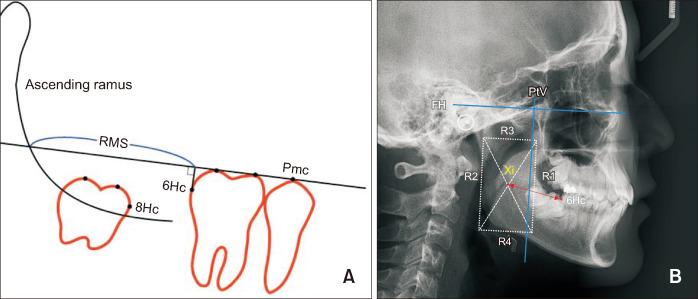

This study assessed 46 L8 from 28 patients using dental study models, panoramic radiographs, and lateral cephalograms obtained during L7 extraction (T1) and completion of L8 eruption (T2). At T2, samples were categorized as acceptable (A-group) or unacceptable (U-group) based on the American Board of Orthodontics index. L8 angulation and position, retromolar space, distance between the Xi point and mandibular first molar (L6), and Nolla stage were compared between the groups to identify the predictive factors for successful eruption.

At T2, 58.7% of L8 exhibited acceptable occlusion. Age at T1 was significantly higher in the U-group than that in the A-group. Angles ∟6-MnP and ∟8-MnP differed significantly between the groups at T2. Xi-L6 distance was considerably longer in the A-group than that in the U-group at T1 and T2. Younger age at extraction and Xi-L6 distance at T1 affected the acceptable occlusion.

Younger age at L7 extraction and adequate eruption space (Xi-L6 distance) appear to be the key factors for achieving acceptable L8 occlusion.